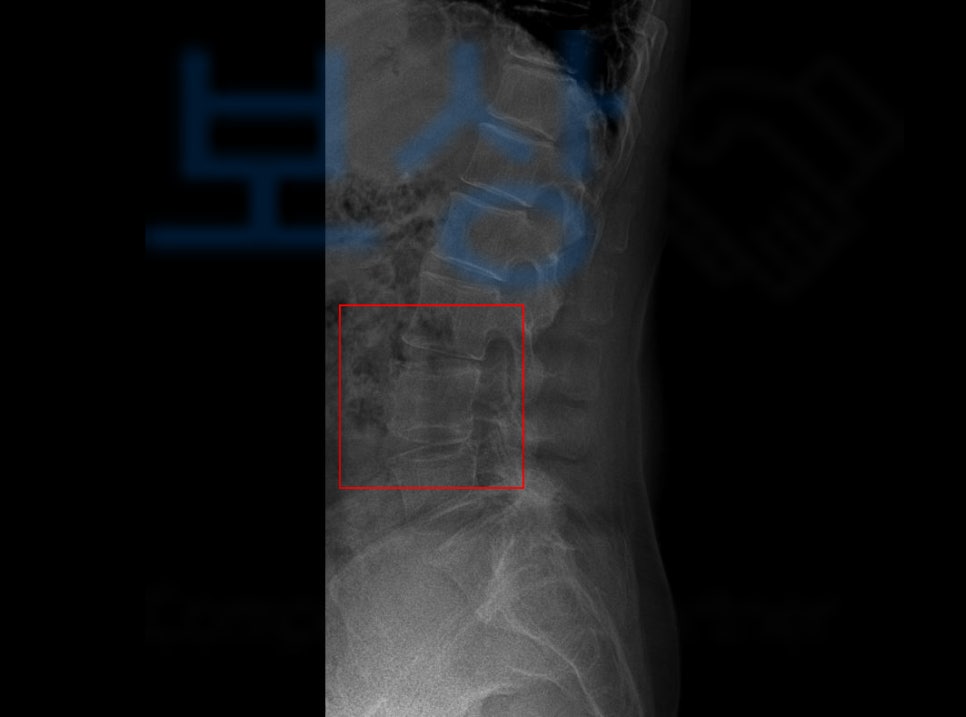

김@@님 께서도 단순 엉덩방아였지만 병원에 내원하여 정밀검사를 받아보니 요추4번의 척추압박골절 진단을 받으셨습니다.

위 사진을 보시면 요추4번부위가 별로 찌그러지지 않은 것 같은시죠? 하지만 척추압박골절은 시간이 가면서

점점 척추체에 압력이 가해져

마치 깡통캔이 찌그러지듯

더욱 골절이 진행되는데요,